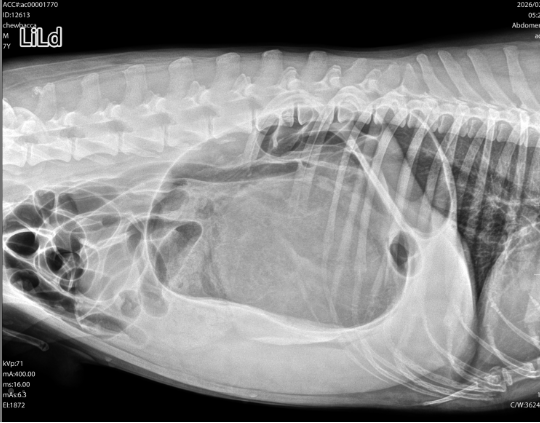

Smokey es más que una mascota, es mi familia. Desde el 5 de marzo, hemos estado viviendo una pesadilla. Lo que empezó como un vómito constante terminó en un diagnóstico crítico: vólvulo gástrico (estómago torcido).

La batalla ha sido cuesta arriba. Smokey ha luchado contra una neumonía naciente y ahora contra una pancreatitis que mantiene parte de su órgano comprometido. Verlo bajo sedación y con analgésicos fuertes para soportar el dolor me rompe el corazón, pero él sigue luchando.